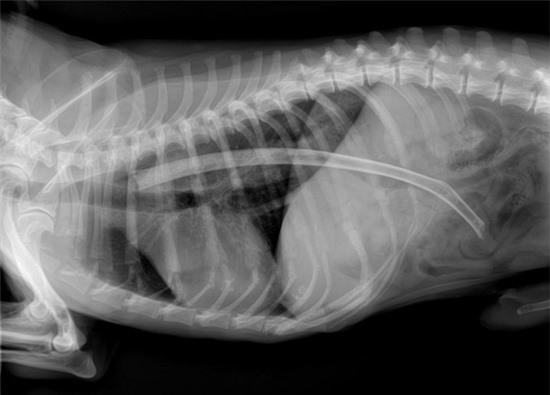

Khóc thét trước những dị vật nguy hiểm nằm gọn trong dạ dày thú cưng 3

Ảnh X-quang bụng của chú chó giống pit bull Yoda sau khi nuốt chửng cây gãi lưng dài 35cm.